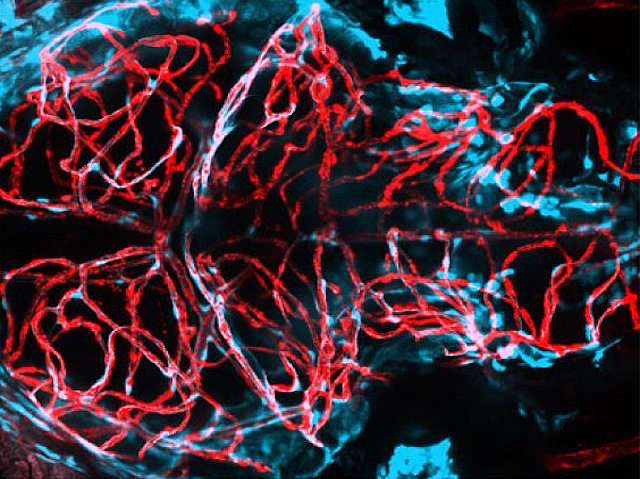

Vulnerabilitat Vascular

La malaltia dels vasos cerebrals menuts (VCM) és una de les principals causes d’ictus i demència però, com que els vasos cerebrals humans no són accessibles per a la investigació, és difícil estudiar-la directament. Ací, un model de VCM en peix zebra revela el paper de mutacions en el gen foxf2. Els peixos amb foxf2 mutat presenten perícits anormals, les cèl·lules que envolten els vasos sanguinis i que són clau per a la formació i l’estabilitat vascular.

Imatge del treball de Merry Faye E Graff i col·laboradors/es

Alberta Children’s Hospital Research Institute, University of Calgary, Calgary, Canada, Department of Biochemistry and Molecular Biology, University of Calgary, Calgary, Canadà